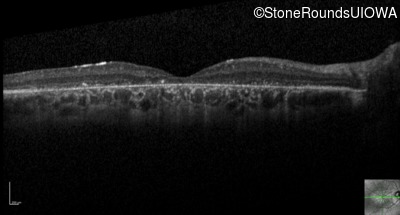

Optical Coherence Tomography - Right - 10/200

Exemplar / OCT Stack